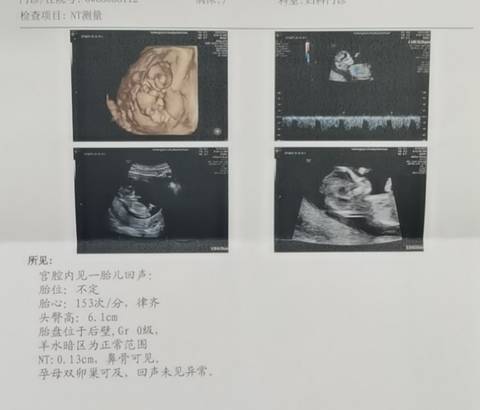

请问这NT能看出男孩女孩吗?大家帮我看下男孩女孩呢预产期刚好35周岁选择去做无创

journal_insert_pic_1675944863